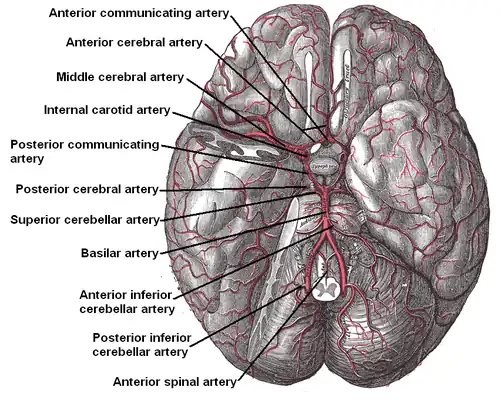

The arteries of the base of the brain.

The arteries of the base of the brain. -